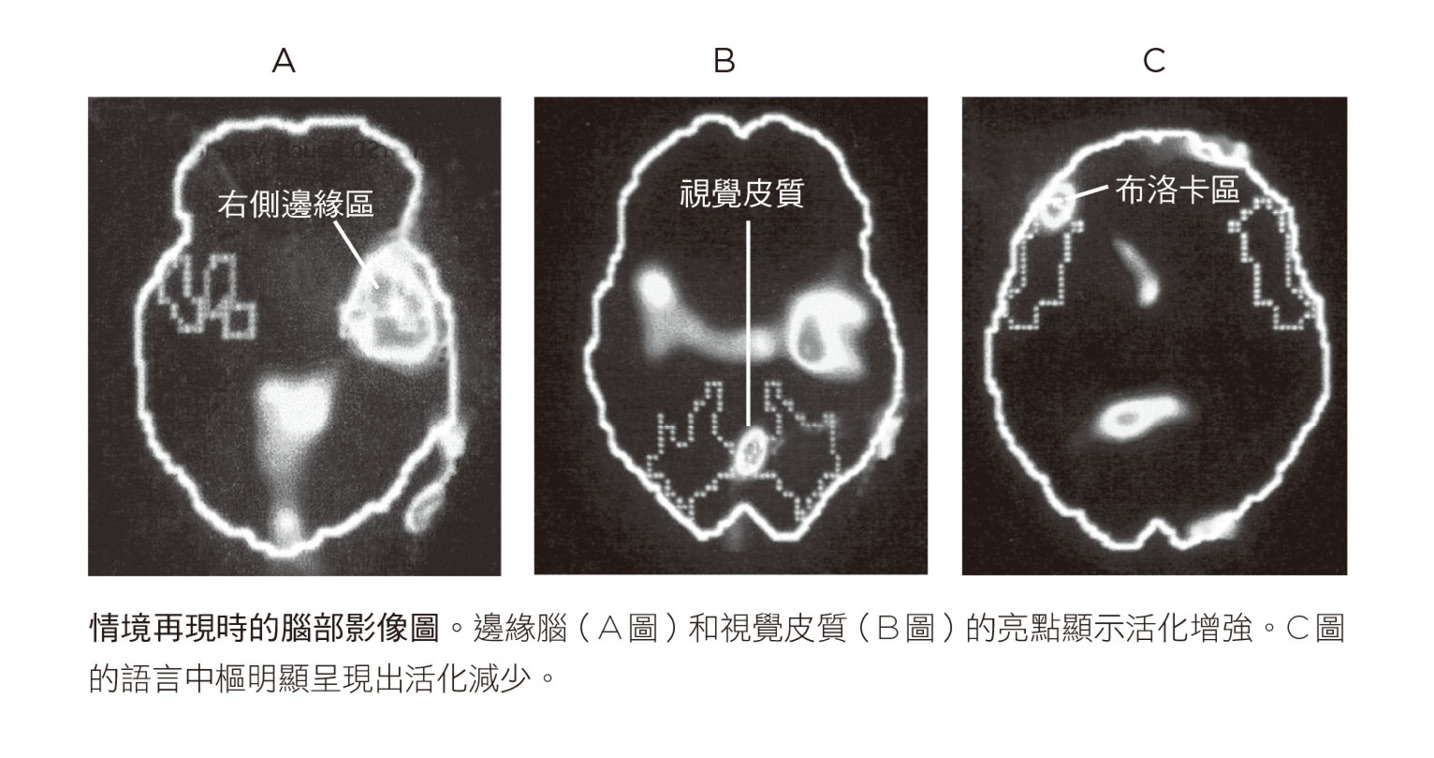

八位受試者都完成實驗之後,史考特.羅許和數學專家及統計學者比較腦部在情境再現與接受中性刺激時的活化狀態,製作出合成影像,幾個星期後,他將結果寄給我,如下圖所示。我把這些腦部影像圖貼在廚房冰箱上,接下來幾個月每晚都盯著看,早年天文學家透過望遠鏡看到新的星座時,大概就像我這樣吧。

影像圖上有一些令人費解的點和顏色,但活化程度最大的區域並不讓人意外,正是腦部中央偏右下方一個紅色的大區塊,即邊緣區,或稱情緒腦。目前已知強烈的情緒會活化邊緣系統,尤其是名為杏仁核的區域。杏仁核會在危險逼近時發出警告,並啟動身體的壓力反應。我們的研究清楚顯示,遭受創傷的人一旦接觸跟自己的特定經驗有關的影像、聲音或想法,如瑪莎的案例,即使事件已過了十三年,杏仁核都會發出警報。這個恐懼中樞被活化後會釋放壓力荷爾蒙和神經衝動,促使血壓上升、心跳加快,以及增加氧氣吸收,讓身體做好戰或逃的準備。1即使瑪莎很清楚自己正安靜地躺在掃瞄儀裡,但繫在手臂上的監測器仍記錄到這個狂亂激發的生理狀態。

● 無法言喻的恐懼

最出乎我們意料的發現,是左額葉一個稱為布洛卡區的白點,此處的顏色改變意味著這個腦區的活動量顯著下降。布洛卡區是腦部的語言中樞之一,中風病人的這個部位常因血液供給中斷而受到影響。布洛卡區功能異常,你就無法將想法和感受訴諸於語言或文字。影像圖顯示,創傷情境一再現,布洛卡區就會「斷線」,換言之,這些證據顯示創傷對大腦造成的生理損害不亞於中風,甚至可能有部分還雷同。

語言失效時,揮之不去的影像便佔據這段經驗,以噩夢和情境再現的形式一再出現。從受試者的腦影像圖可以發現,相對於布洛卡區的不活化,布羅德曼十九區會亮起,這區域位於視覺皮質,外界圖像進入大腦後會先被送到這裡暫存。我們對於這個腦區在創傷事件發生很久之後仍會活化感到驚訝,因為正常情況下,原始圖像送到十九區後就會立刻分散到大腦皮質的其他部位,好讓我們詮釋所見事物的意義。但如今我們親眼目睹受試者這一個腦區又亮了起來,彷彿創傷正在實際發生。

● 偏向大腦的一側

影像圖也顯示當受試者經歷情境再現時,只有右側大腦亮起來。目前有許多科學文獻和大眾讀物提到左、右腦的不同。一九九○年代早期,我聽說有些人開始把人類分為左腦人(理性、有邏輯的人)和右腦人(重視直覺、有藝術天分的人),我不是很在意這種說法,然而我們的掃瞄結果清楚顯示,過去的創傷影像會使右腦活化,左腦不活化。